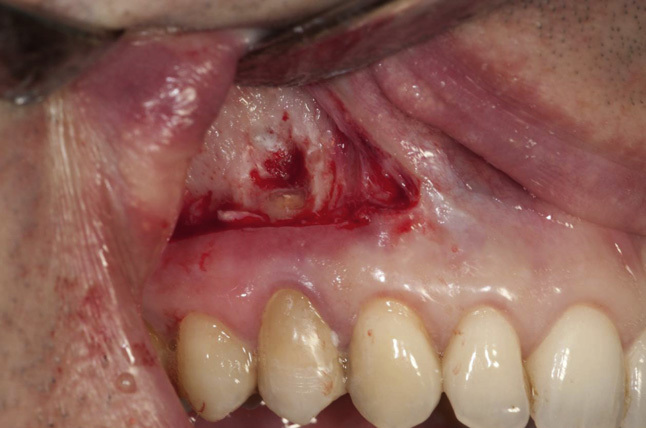

Apikal rezeksiyon dişin çene kemiği içinde yer alan kök ucundaki iltihaplı dokunun cerrahi işlemlerle alınması işlemidir. Apikal rezeksiyon ile dişlerin çekilmeden önce son bir değerlendirilmesi yapılır. Yapılan bu işleme dişlerin kök ucu rezeksiyonu da denilebilir. Kök ucu rezeksiyonu ile çeşitli tedaviler uygulanıp başarısızlık elde edilen diş kökleri kalıcı olarak iyileştirilmektedir. [caption id="attachment_6693" align="alignright" width="400"]

apikal rezeksiyon ameliyatı[/caption]

Apikal Rezeksiyon Ameliyatı

Apikal rezeksiyon ameliyatı yapılacak kişinin öncelikle kanal tedavisine ihtiyacı olup olmadığı belirlenir. Rezeksiyon öncesinde yapılması gereken diş çürüğü veya diş eti hastalığı gibi durumlar varsa önce bunlar tedavi edilir, daha sonra rezeksiyon ameliyatı uygulanır. Apikal rezeksiyon ameliyatına başlanmadan önce ilgili dişe lokal anestezi uygulanır. Ardından diş köklerinin çıkarılabilmesi için diş etlerine çeşitli kesiler atılır. Lazer yardımı ile diş açığa çıkarılır ve daha sonra dişin kökleri çekilir. Bununla beraber görülen çürük veya hastalıklı diş kısımları da diş hekimi tarafından alınır. İşlem bittikten sonra apikal rezeksiyon uygulanan bölge steril serum ile yıkanır ve kesilen alanın sterilize edilmesinden sonra dikiş atılır. Kök ucu alınan dişin üzerine geçici diş kaplama ya da dolgu ile kapama işlemi uygulanır. Diş hekimi tarafından belirlenecek süre sonrasında ise bu geçici kaplama, daimî kaplama ile değiştirilir.